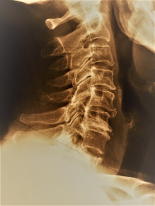

ストレート・ネッグ スワン・ネッグ 椎間孔の極小化 カルシウムの沈着

上の状態の頸部では、慢性的な肩こり・手のしびれ・冷感・脱力・感覚の低下等の他に、頭痛・眼の奥の痛み・噛み合わせの不具合等に悩まされます。